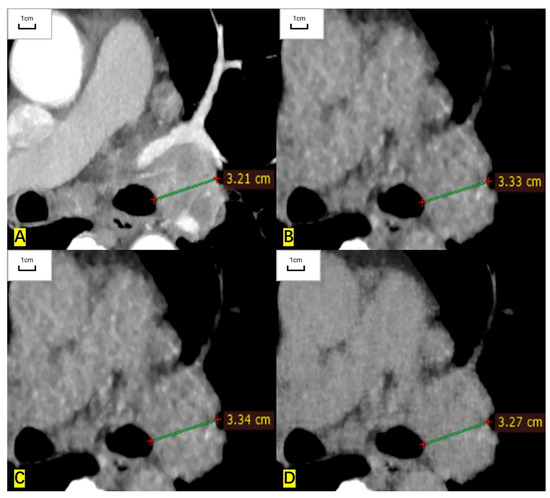

Figure 1.

A 57-year-old man had a measurable target lesion in the upper lobe of the left lung and the histological result was lung adenocarcinoma. (A) The long diameter measured on the contrast-enhanced CT image is 33.2 mm. (B) The measured long diameter on the ASIR-V-80% reconstructed image is 33.9 mm. (C) The measured long diameter on the DLIR-M image is 34.2 mm. (D) The measured long diameter on the DLIR-H images is 33.5 mm. The long diameter is overestimated by 2.1%, 3.0%, and 0.9%, respectively, compared with that of contrast-enhanced CT.

For RECIST-defined pulmonary target lesions, the correlation coefficient of measured diameter between ULDCT and contrast-enhanced CT was 0.999 (95% CI: 0.998 to 0.999), 0.998 (0.997 to 0.999), and 0.999 (0.999 to 1.000) for ASIR-V-80%, DLIR-M, and DLIR-H images, respectively. For mediastinal lymph nodes, the correlation coefficient was 0.997 (0.995 to 0.999), 0.997 (0.995 to 0.998), and 0.999 (0.998 to 1.000), respectively. For hilar lymph nodes, the correlation coefficient was 0.993 (0.979 to 0.997), 0.995 (0.984 to 0.998), and 0.997 (0.991 to 0.998), respectively. The measured diameters of target lesions in ULDCT were highly correlated with those in contrast-enhanced CT (Table 2, Figure 1 and Figure 2).